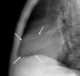

Pericardial lipomatosis